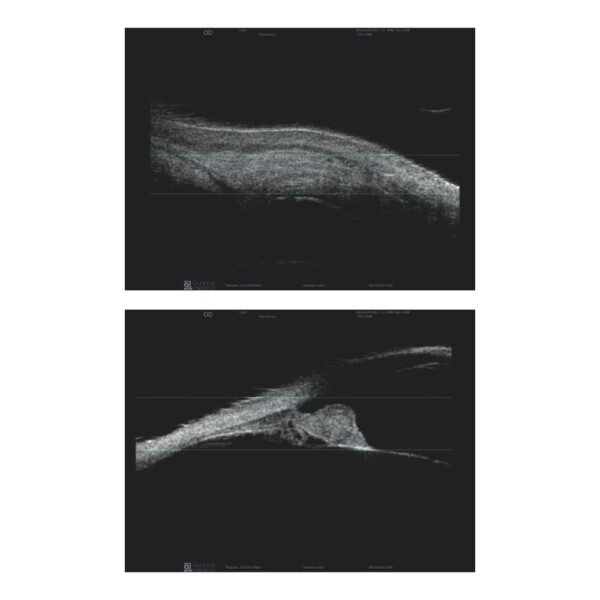

A Quantel Medical, líder mundial em ultrassom ocular, apresenta sua nova plataforma modular de ultrassom A/B/S/UBM, o ABSolu. Esta nova plataforma oferece uma qualidade de imagem excepcional através da sua nova interface ergonômica e design moderno.